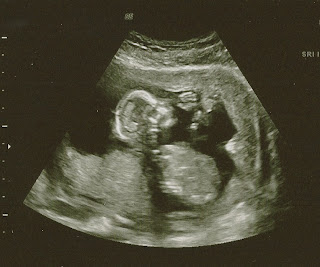

Okay, ready? Surprise!!

The Daddy. . .